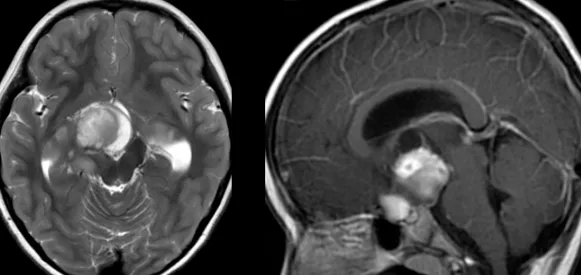

核磁一出,阿康妈妈立刻傻眼。“右侧基底节区及下方占位、鞍区占位”这几个字怎么也看不进自己的脑子,反而令她出了一身冷汗。

由于肿瘤涉及的解剖结构,如视神经、视交叉、视束、丘脑底垂体轴、第三脑室、脑底动脉环等,令阿康出现了视力下降、头痛、呕吐等症状,如果不及时治疗,随之而来的可能还有生长发育异常、认知发育缓慢和心理、行为功能障碍、阻塞性脑积水等……

巴教授认为,这是一个双侧视神经系统下丘脑胶质瘤,并在两个视束内延伸。为尽可能地保全原有视力、解除巨大占位效应,较为合适、有效的治疗方法是手术切除。

因此,针对这次手术,巴教授携国内专业手术团队,强强联合,成功为阿康次全切巨大视路胶质瘤。双侧视神经、下丘脑、脑干区域内肿瘤次全切除,仅神经表面参与小部分肿瘤,术中行神经电生理监测、术中神经导航技术,实现安全切除。

术后,阿康顺利转到普通病房,术后复查MR显示肿瘤得到次全切除,孩子的原有视力得到保留。看到儿子术后恢复良好,无新发神经功能损伤,阿康妈妈十分欣慰。